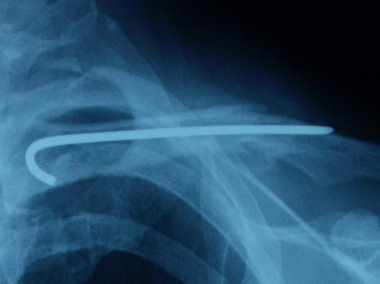

4月30日に診察へ行ったときの骨の状態は

泣きたくなるほどの微妙な骨の再生やってんけど

今日診察へ行ってきたら

ほぼ完治に近い状態まで骨は再生されてました。

骨って一旦再生が始まると成長が早いのでしょうか。

前回の骨の画像が分かりにくかった感じがしたので

今回は4月30日と今日の画像を並べてみます。

骨は引っ付いても左右の肩の幅は若干違いもありますし

肩も下がってます。

それに、今まで腕を肩以上上げることを禁じられてたので

肩こりだと思うんですが、今でも肩が『痛い』と言ってます。

これからは腕も体も自由に動かして肩こりと運動不足を

解消してもらおうと思います。

まぁ、きっと我が家のおいやんならこの先も

どこかしこ『痛い 痛い』と言い続けるでしょうけどね。( ̄ェ ̄;)

骨折をした時は、幼稚園の女の子相手のケンカでも負けるんちゃうか?

って言うくらい鎖骨と肩を大事に大事に守ってたけど

今度の診察でワイヤーともおさらばだそうです。

とりあえず、長い長い鎖骨骨折物語は無事完結です。

骨折治療期間 王子 ほぼ1ヶ月。 おいやん 約3ヶ月。

痛い 痛いと言った数 王子 少数。 おいやん 言いすぎ。

治療費 約1万 おいやん 約10倍くらい(使いすぎ。)